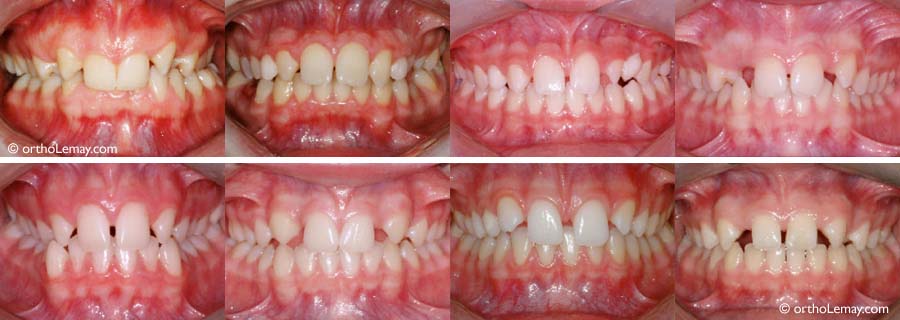

Les dents étroites, souvent des latérales supérieures, sont une des causes principales d’espaces interdentaires affectant les incisives supérieures. Pour optimiser la fonction et l’esthétique, il est préférable de corriger la malposition des dents avant de les faire élargir de façon “définitive”.

• (A) Dentition avec 2 latérales étroites (“grain de riz”) avant le traitement.

• (B) Après les corrections, les espaces sont distribués de façon optimale pour permettre d’élargir les latérales. Les autres aspects e la malocclusion ont aussi été corrigés.